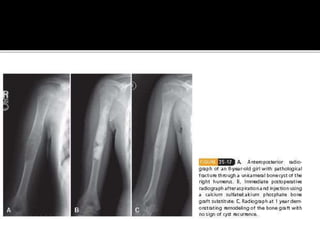

 Developmental/reactive lesion

 1st – 2nd decades. M:F = 2:1

 Any extremity; most common – proximal

humerus and femur. Ilium and calcaneum.

 Active during skeletal growth and heal

spontaneously at maturity

 Asymptomatic unless pathological fracture

 Radiologically – Centrally located, purely

radiolucent lesion which concentrically

expands the cortex. No cortical destruction

 Cyst filled with straw colored fluid.Thin

fibrovascular lining.

 Observation

 Aspiration

 Injection of steroids/bone marrow/bone graft

substitutes

 Curretage